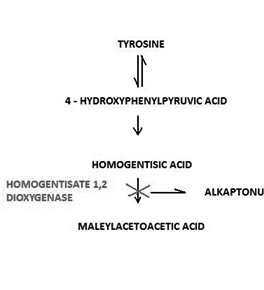

Alcaptonuria is an extremely rare metabolic disease and is defined as an autosomal recessive inherited deficiency of the hepatic enzyme oxidase of the homogentisic acid1,2 (Figure 1). Deficiency of the enzyme causes accumulation of the homogentisic acid in the cells and the body fluids. The disease is characterized by the following three specific conditions, excretion of homogentisic acid in the urine, arthritis and ochronosis. Homogentisic acid accumulates and is polymerized into a blue-black pigment that is ultimately deposited in the skin, cartilage and collagenous tissues. Specifically, pigment deposition can be seen in skin, bones, articular cartilages, ear and sclera, heart endocardium and valves, and kidneys (the so called ochronosis).3 The accumulation eventually causes severe degeneration of the spine and peripheral joints, like knees, hips and shoulders.

Figure 1 The catabolic path of tyrosine. Deficiency of the hepatic enzyme oxidase of the homogentisic acid causes alcaptonuria due to the accumulation of homogentisic acid.